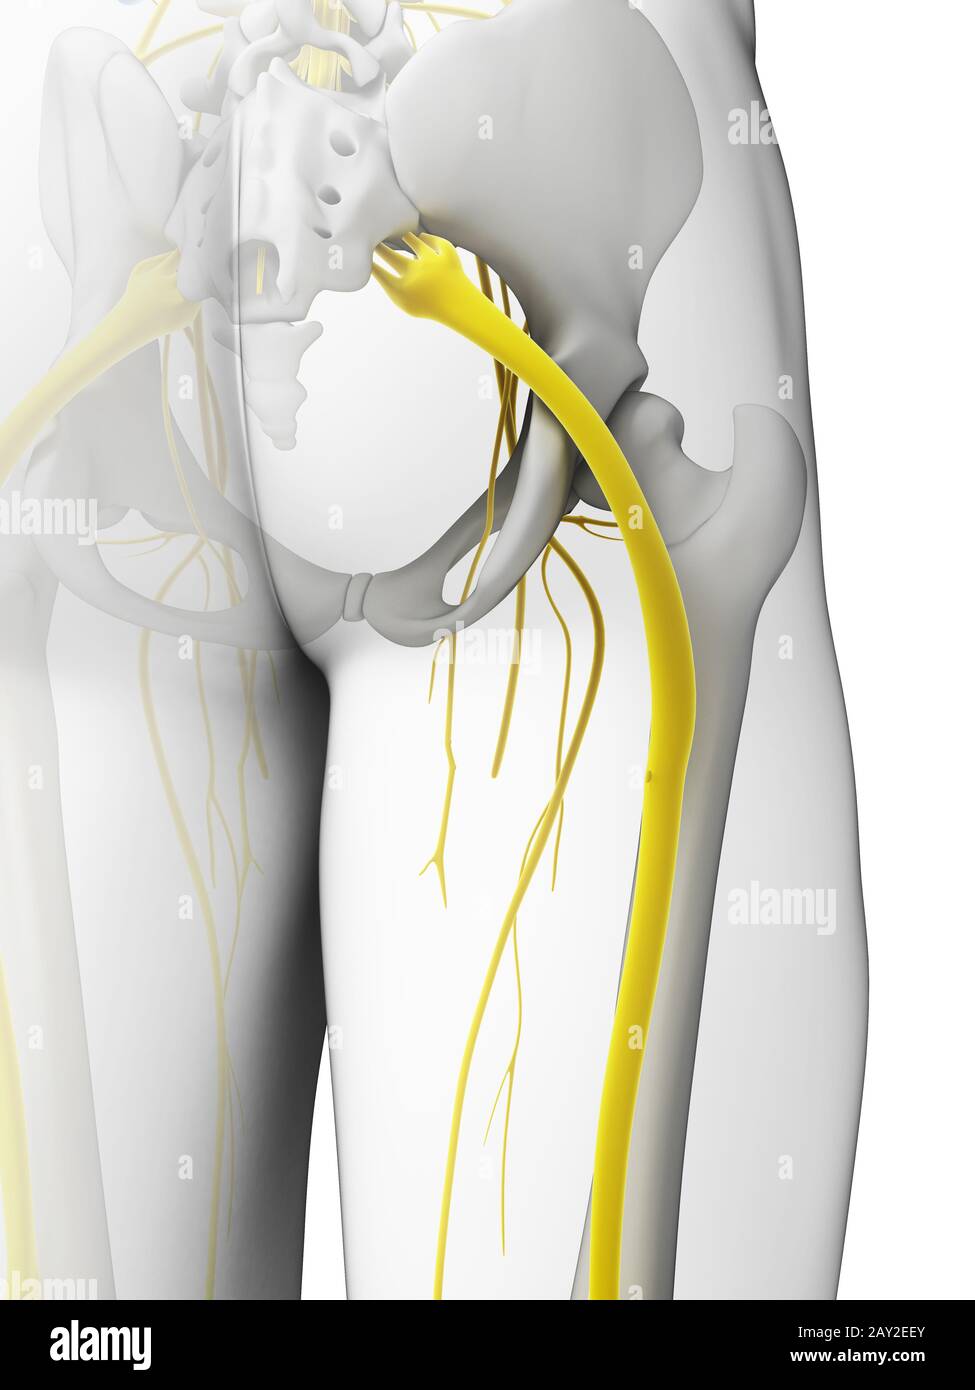

Rendu 3d illustration - nerf sciatique Banque D'Imageshttps://www.alamyimages.fr/image-license-details/?v=1https://www.alamyimages.fr/rendu-3d-illustration-nerf-sciatique-image343648003.html

Rendu 3d illustration - nerf sciatique Banque D'Imageshttps://www.alamyimages.fr/image-license-details/?v=1https://www.alamyimages.fr/rendu-3d-illustration-nerf-sciatique-image343648003.htmlRM2AY2EEY–Rendu 3d illustration - nerf sciatique